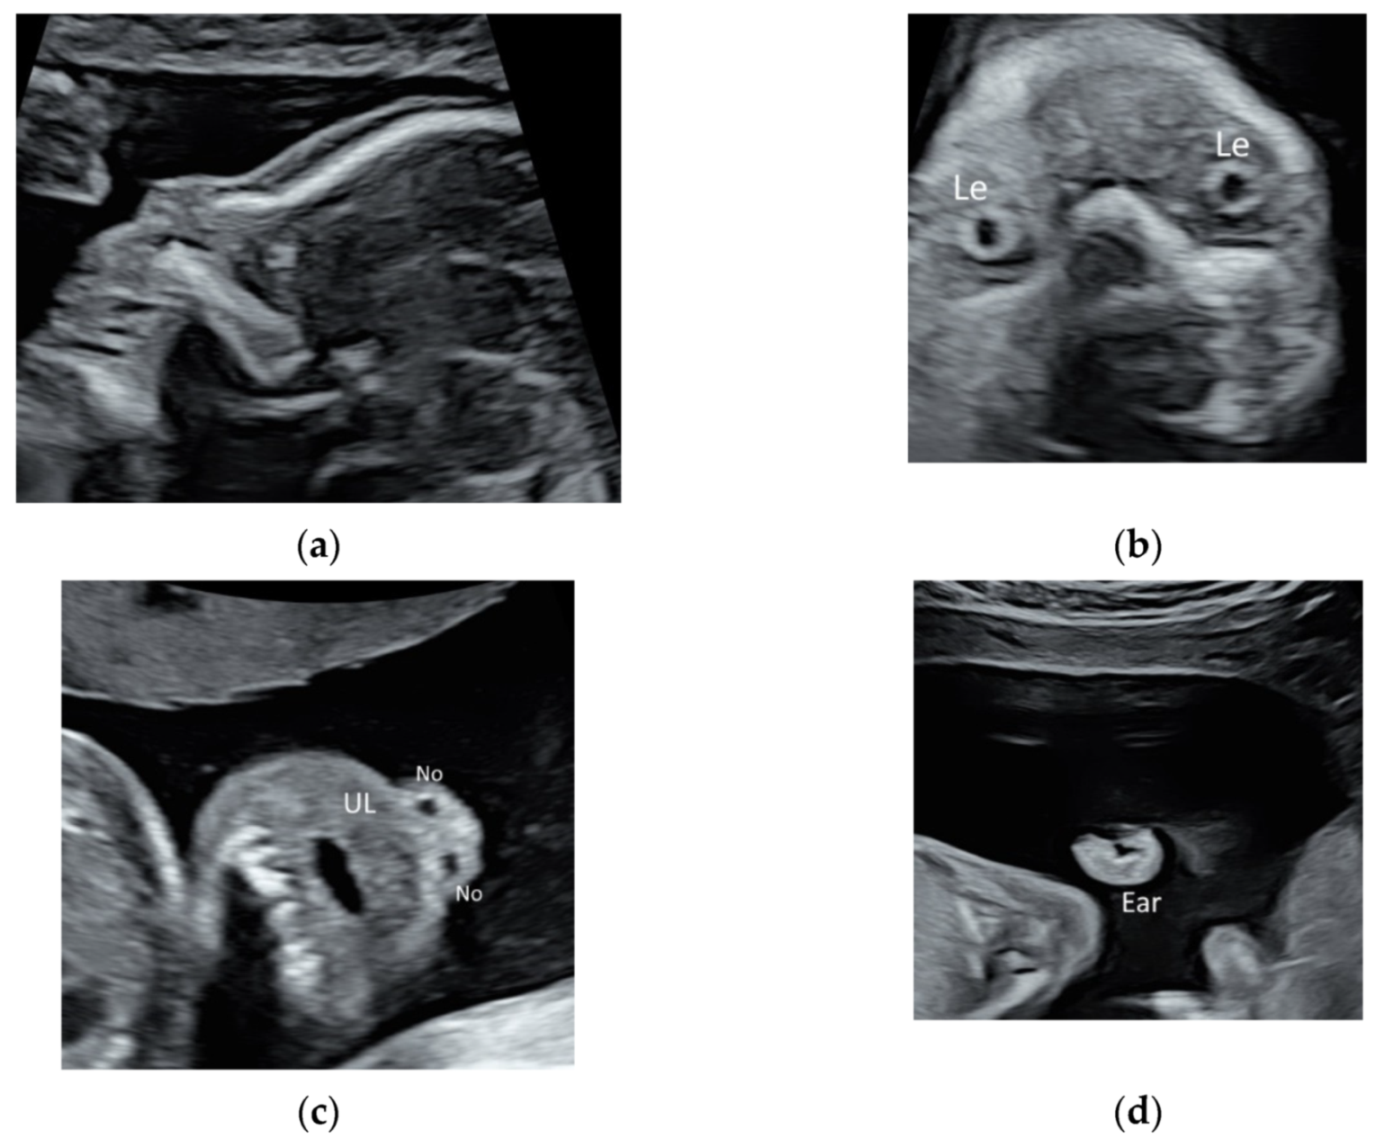

2.2. Face and Neck

While the prenatal detection of cleft lip is high, the detection rate of subtle abnormalities of face such as low-set or posteriorly rotating ear, triangular face, down-slanting palpebral fissures, or a long and marked philtrum remains low [14,15]. These subtle abnormalities may be features of rare but severe genetic disorders such as 5p deletion syndrome or RASopathy, which require chromosome microarray analysis or targeted sequencing for RASopathy genes. As such, it is important to perform a detailed ultrasound scan to evaluate fetal face in fetuses especially if they have large NT, heart defects, or unusual findings [14,15]. High-resolution ultrasonography allows the clear visualization of facial profile, lens, nostrils, lips, maxilla, and ears (Figure 3a–d, Video S3a,b). Recently, a new sonographic sign, the ‘superimposed line’ sign, is suggested for evaluation of the secondary palate by assessment of the vomeromaxillary junction in the midsagittal view of the palate [16] (Figure 3a).

Figure 3.

High-resolution ultrasonography of the fetal face at 20 weeks’ gestation: (a) mid-sagittal view showing facial profile, (b) coronal view showing both lens (Le), (c) coronal view showing the upper lip (UL) and two nostrils (No), and (d) sagittal view showing the ear.

Larynx and its movement can be assessed by prenatal ultrasound (Figure 4 and Video S4). In at-risk fetuses such as those with laryngeal atresia [17] and congenital diaphragmatic hernia, prenatal ultrasound allows systematic examination of the larynx, including vocal cords to detect laryngeal anomalies [17,18].

Figure 4.

High-resolution ultrasonography of the fetal neck at 21 weeks’ gestation: sagittal view showing larynx (Lar) and trachea (T).